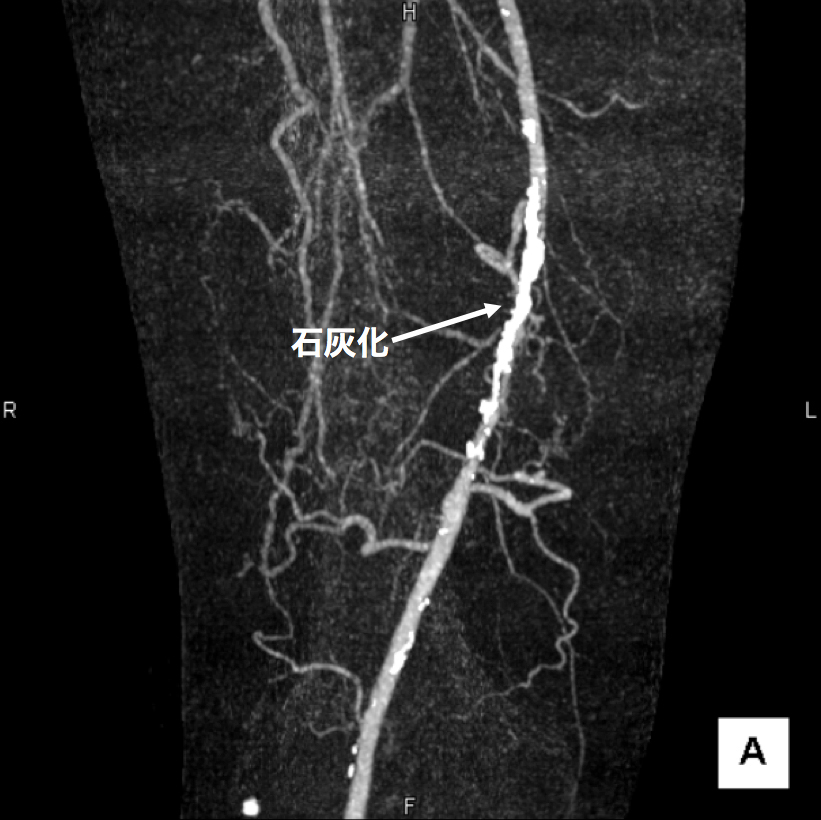

3、造影CT検査 造影剤を点滴しながらCTを撮像することで、血液の流れ、血管の状態などを把握します。情報量が多く治療方針を決定する場合に役立つので当院では特に力を入れている検査です。(図2、3、4)

【図2】下肢造影CT検査 この画像は血管の立体的な走行の把握に有用です。 右足大腿部の血管に強い石灰化(動脈硬化の変化)があります。